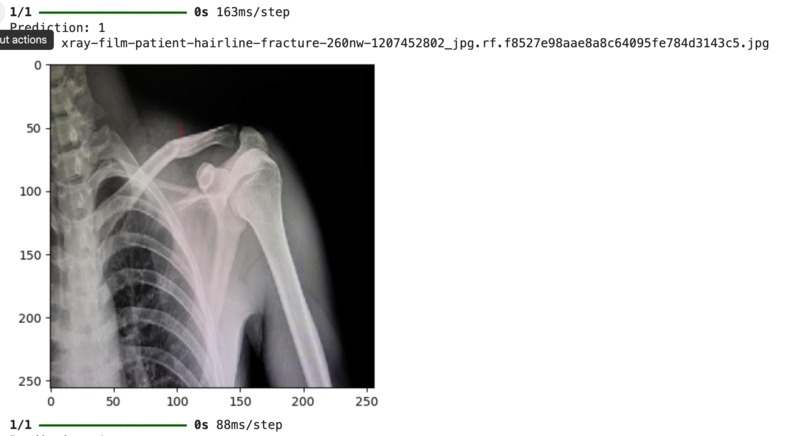

Takes in images of bone x-rays and determines whether or not the bone is fractured or normal

Used Python in Colab, a binary classification system for the two fractured vs. not fractured classes, used the sigmoid function with the binary classification